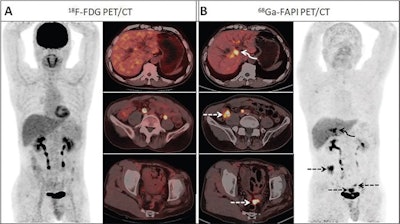

Chinese researchers compared gallium-68 (Ga-68) FAPI-PET/CT with F-18 FDG-PET/CT for detecting primary tumors and nodal and distant metastases in patients with biliary tract cancer. They found FAPI-PET/CT was superior and showed a significant improvement in the clinical management of patients.

Results revealed the sensitivity of Ga-68 FAPI-PET/CT was higher than that of F-18 FDG-PET/CT for detecting primary tumors, nodal metastases, and distant metastases.

"Ga-68 FAPI-PET/CT was superior to F-18 FDG-PET/CT for detecting the primary tumor and nodal and distant metastases," the researchers stated.

In addition, Ga-68 FAPI-PET/ CT resulted in new oncologic findings in 10 of 18 patients and upgraded tumor staging or restaging in five of 18 participants compared with F-18 FDG PET/CT, the researchers found.